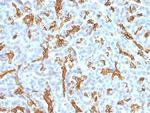

Cytokeratin 19 (KRT19) (Pancreatic Stem Cell Marker) Monoclonal Antibody (KRT19/799, KRT19/800)

Cytokeratin 19 is part of a subfamily of intermediate filament proteins and are characterized by a remarkable biochemical diversity, represented in human epithelial tissues by at least 20 different polypeptides. Cytokeratins range in molecular weight from 40-68 kDa and isoelectric pH between 4.9 - 7.8. The individual human cytokeratins are numbered 1 to 20. The various epithelia in the human body usually express cytokeratins which are not only characteristic of the type of epithelium, but also related to the degree of maturation or differentiation within an epithelium. Cytokeratin subtype expression patterns are used to an increasing extent in the distinction of different types of epithelial malignancies. The cytokeratin antibodies are not only of assistance in the differential diagnosis of tumors using immunohistochemistry on tissue sections, but are also a useful tool in cytopathology and flow cytometric assays. For example, cytokeratin 19 is not expressed in hepatocytes, therefore, it is useful in the identification of liver metastasis.